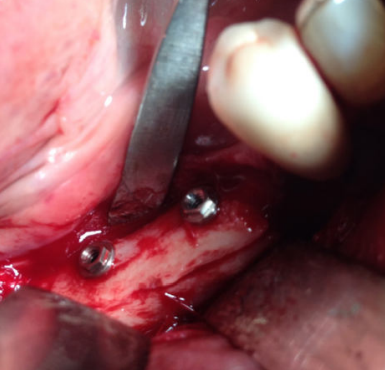

Se planificó la realización de la técnica de Khoury bajo anestesia local y sedación consciente intravenosa. Se realizó una incisión en mucosa libre extendiéndose desde el trígono retromolar hasta el canino homolateral (Figura 3). El colgajo resultante permitió el acceso para la obtención de un injerto en bloque de unos 3 mm de espesor procedente de la línea oblicua externa mandibular del cuadrante homolateral, mediante instrumental piezoeléctrico. La región del trígono retromolar y de la rama ascendente se utilizó para obtener hueso autógeno particulado mediante el uso de un rascador.